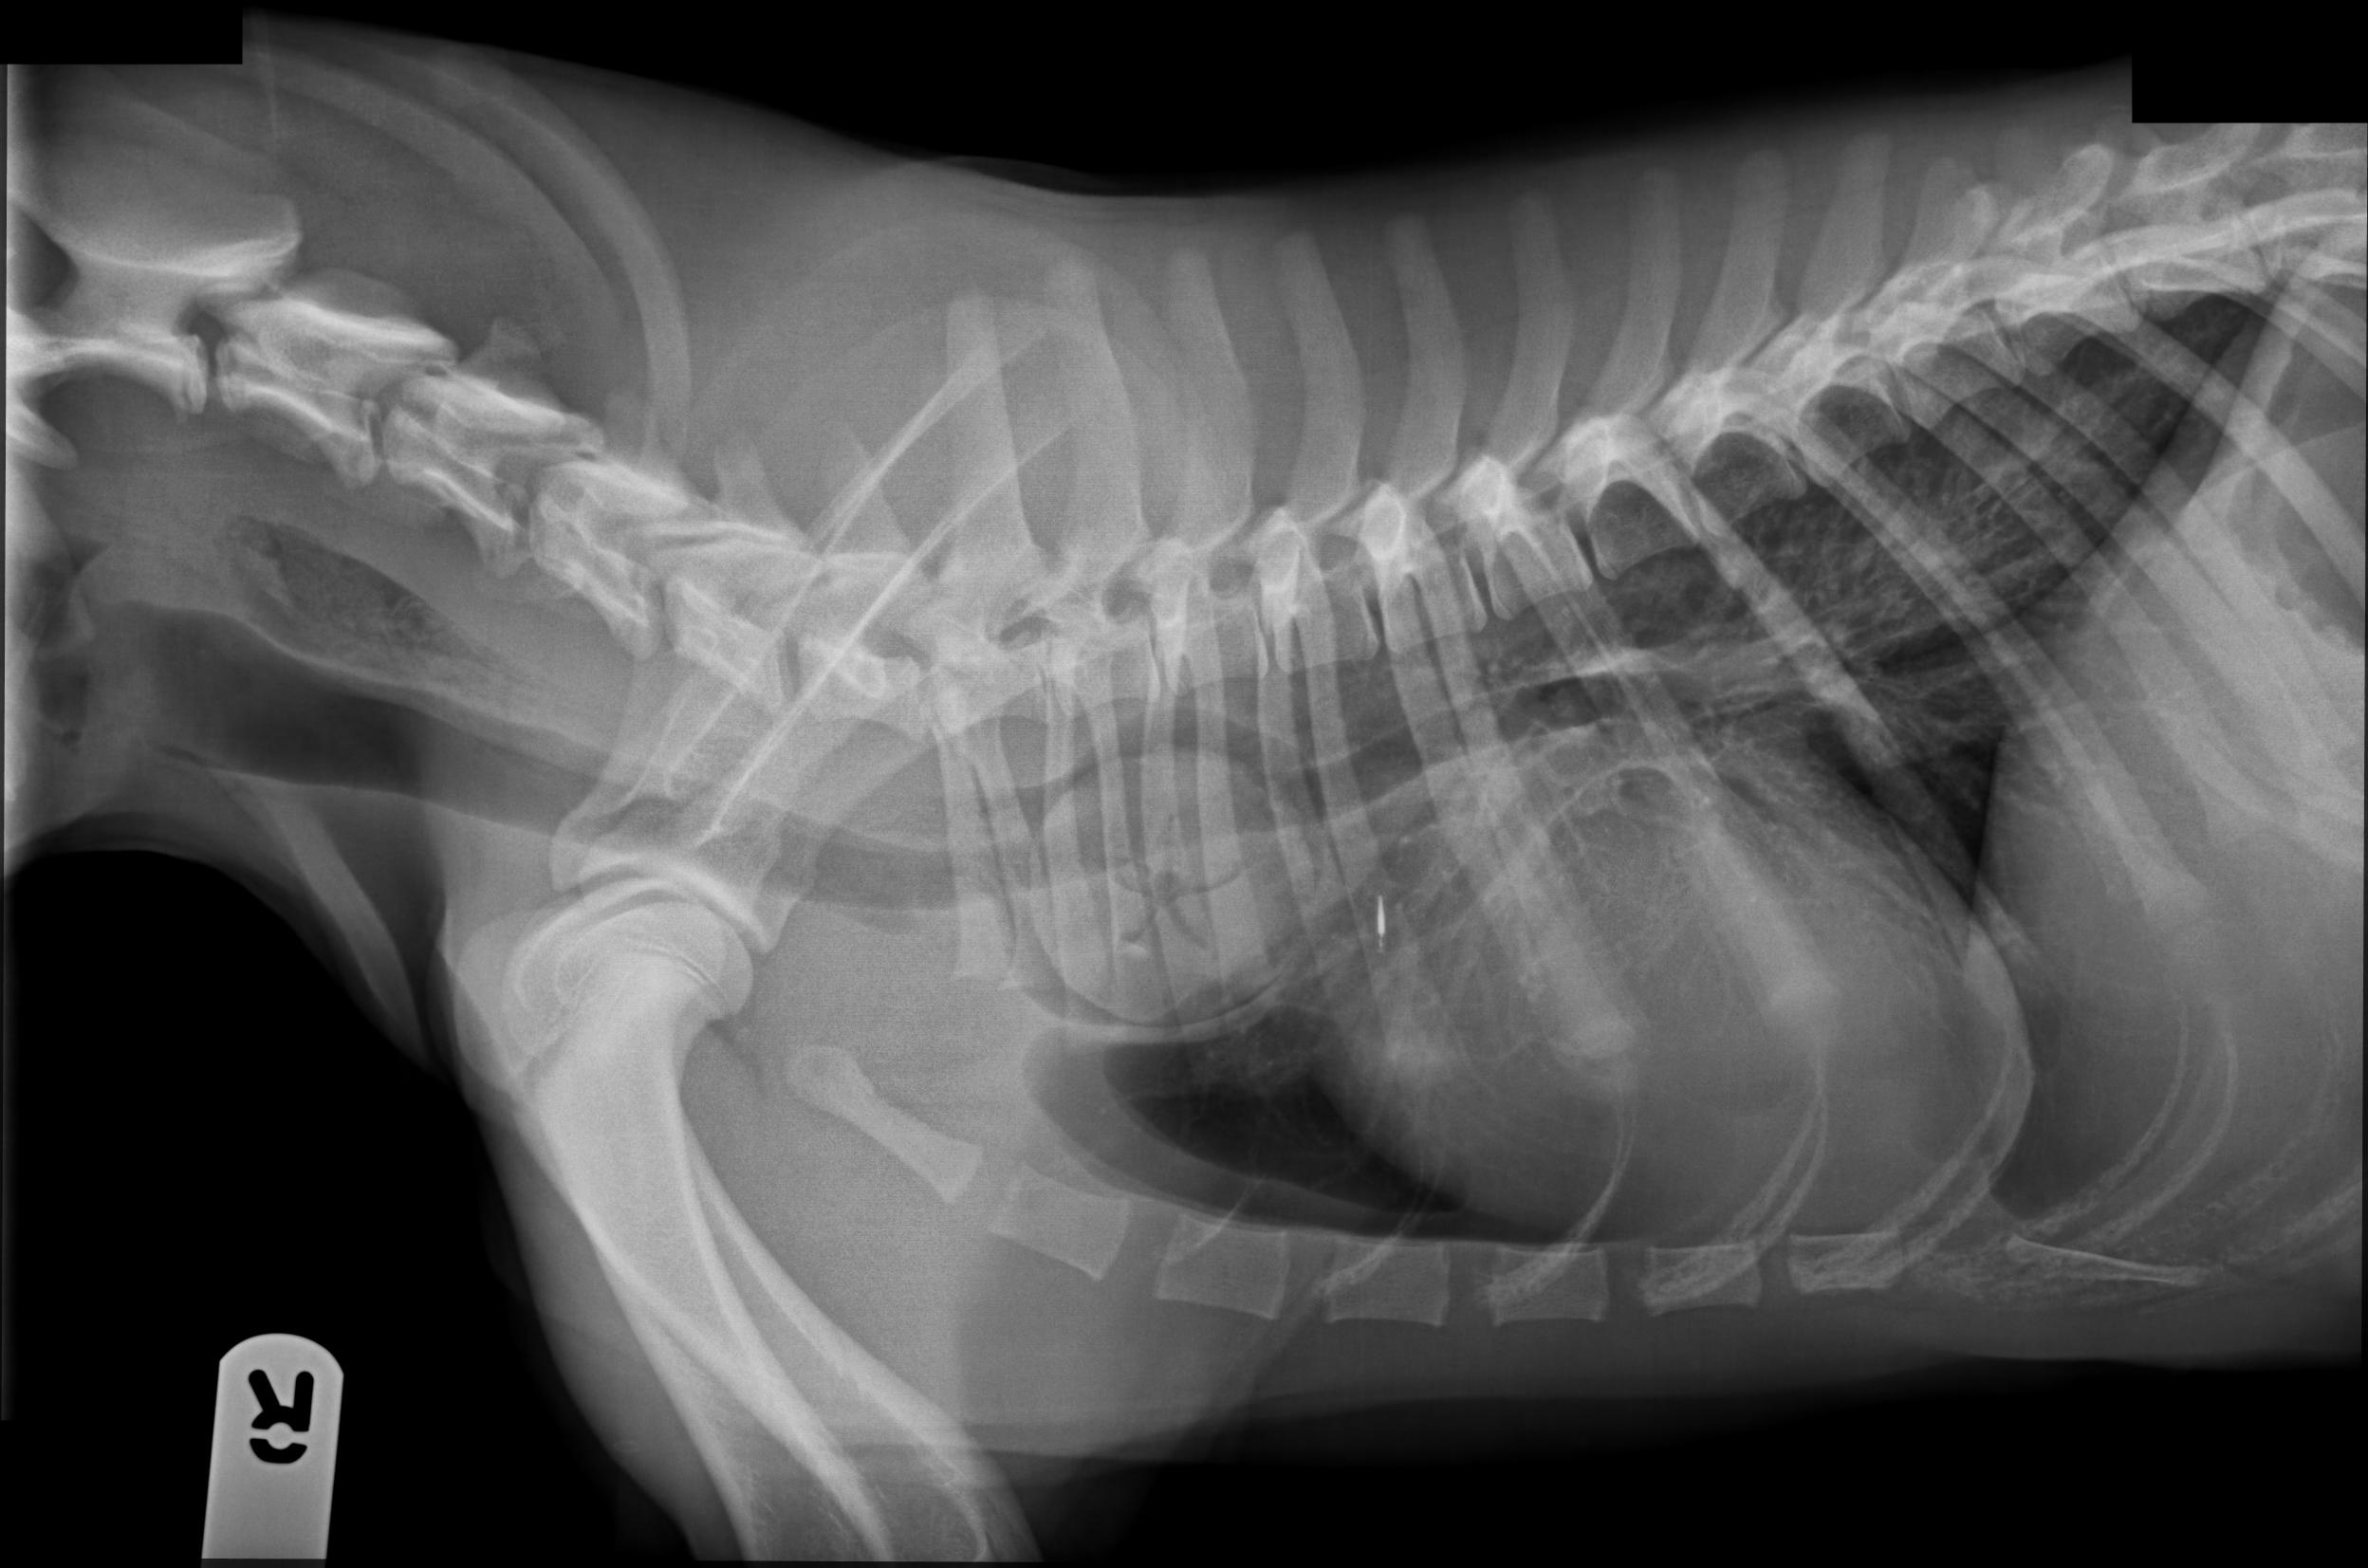

🖼️ My favourite image *(MRI, CT, US, Rads)*

Who doesn’t love a beautiful foreign body!